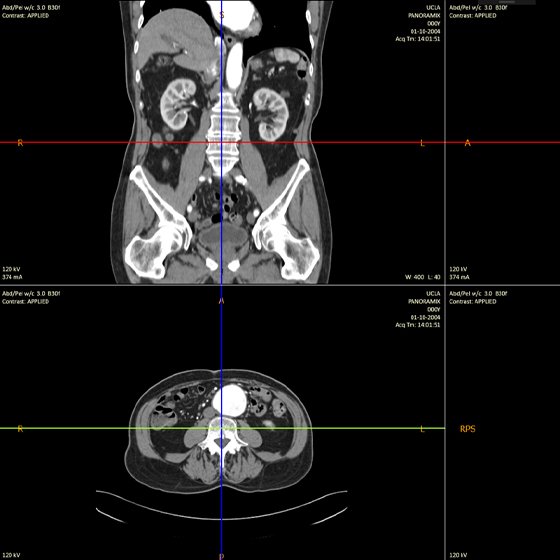

XLINC - CT MRI WOR